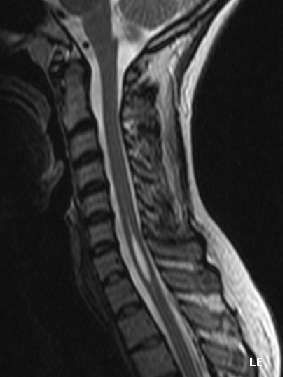

Physicians now use magnetic resonance imaging (MRI) to diagnose syringomyelia. The MRI radiographer takes images of body anatomy, such as the brain and spinal cord, in vivid detail. This test will show the syrinx in the spine or any other conditions, such as the presence of a tumor. MRI is safe, painless, and informative and has greatly improved the diagnosis of syringomyelia.

The possible causes are trauma, tumors and congenital defects. It is most usually observed in the part of the spinal cord corresponding to the neck area. Symptoms are due to spinal cord damage and are: pain, decreased sensation of touch, weakness and loss of muscle tissue. The diagnosis is confirmed with a spinal CT, myelogram or MRI of the spinal cord. The cavity may be reduced by surgical decompression.

Diagnostic technology is another area for continued research. MRI has enabled scientists to see conditions in the spine, including syringomyelia before symptoms appear. A new technology, known as dynamic MRI, allows investigators to view spinal fluid flow within the syrinx. CT scans allow physicians to see abnormalities in the brain, and other diagnostic tests have also improved greatly with the availability of new, non-toxic, contrast dyes.